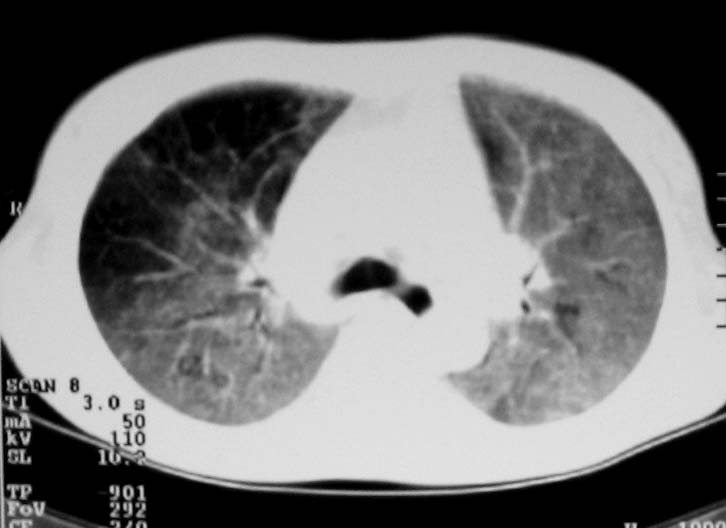

以下是引用zjzjr在2007-9-20 12:29:00的发言:[br]双肺磨玻璃改变,考虑肺水肿.

以下是引用yangzongshan在2007-9-20 18:29:00的发言:[br]两肺毛玻璃样改变,其内可见肺纹理影,无胸腔积液,故考虑肺泡蛋白沉积症

以下是引用276894491在2007-9-20 13:40:00的发言:[br]考虑肺水肿;外源性过敏性肺炎不排除。

以下是引用逸风在2007-9-20 20:45:00的发言:[br]两肺磨玻璃样改变,临床病史短,发热,考虑病毒感染合并右肺代偿性肺气肿.待排肺水肿,病史短,不支持肺泡蛋白沉着症.